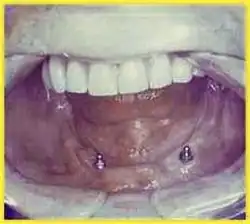

Cover Denture

Als Cover Denture (auch: Deckprothese) bezeichnet man einen Zahnersatz, bei dem noch einige wenige Restzähne im Gebiss vorhanden sind, die mit Teleskopkronen oder Wurzelkappen versehen werden. Die gleiche Funktion können auch Implantate (eingepflanzte künstliche Zahnwurzeln) ausüben. Über diese Kronen wird eine Totalprothese übergestülpt. Die so versorgten Zähne sorgen für einen besseren Halt, insbesondere im Sinne einer Übergangsversorgung, wenn die restlichen Zähne zu einem späteren Zeitpunkt auch noch extrahiert werden müssen. Sie dienen in diesem Fall der leichteren Eingewöhnung an eine Prothese.[59]